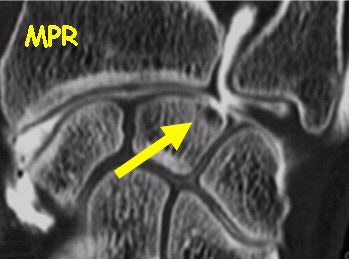

![]() |

Direct and multiplanar reformatted views of wrist CT arthrography show nearly equivalent information for the depiction of ligament tears. Images courtesy of Dr. Sandrine Iochum, CHU Nancy, France.